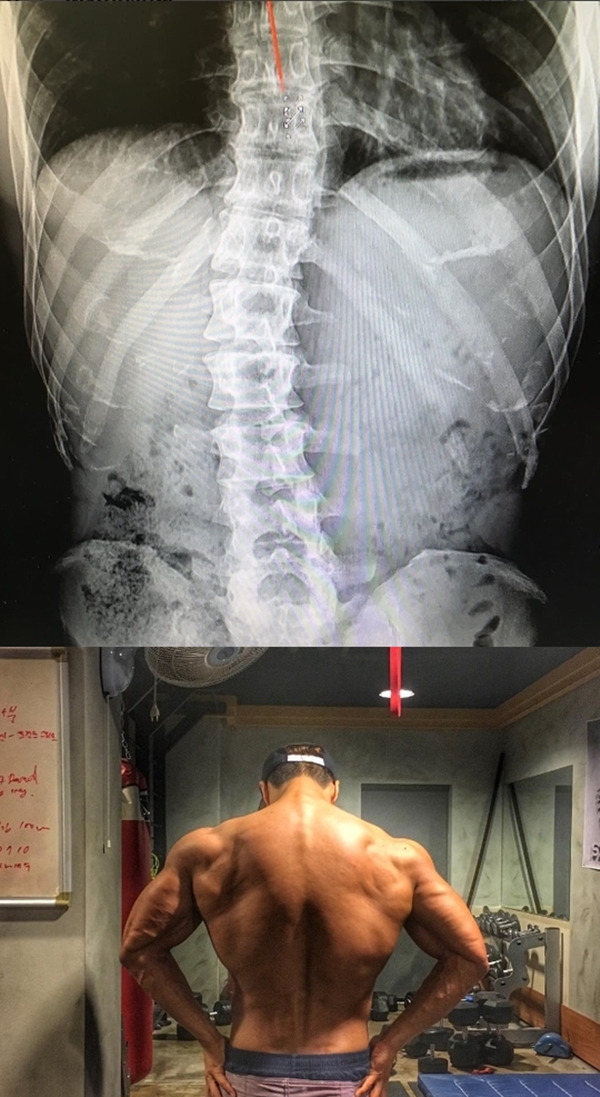

김종국은 4일 오후 자신의 인스타그램에 척추측만증 엑스레이 사진 게재와 함께 "고등학교 때 처음 허리 통증으로 쓰러졌을 때부터 쭉 가지고 있던 척추측만증"이라 입을 뗐다.

이어 김종국은 "딱해서 그래. 동기부여 노력하면 이루어진다. 누가 내 등 사진보고 척추가 참 곧다고 해서 딱해서"라고 덧붙였다.

앞서 김종국은 이날 오전 자신의 인스타그램에 "가슴 운동한 날 기념, 등 샷"이라는 글과 함께 자신의 등 근육 사진을 게재한 바 있다.

이에 일부 네티즌들은 척추측만증을 앓았다면서 어떻게 이런 근육을 만드냐며 공익근무요원에 대해 의혹을 제기했다.